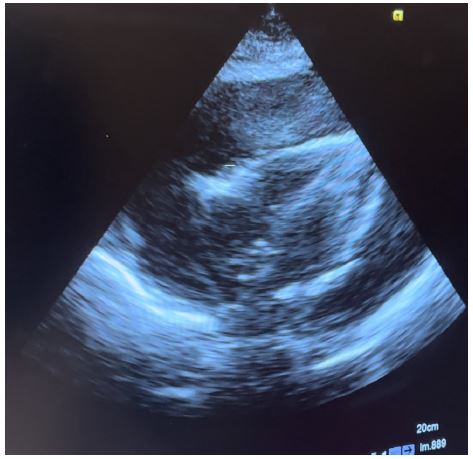

Presenting a 50-year-old immunosuppressed patient who was referred to our hospital for management of massive pre-tamponade pericardial effusion in respiratory distress. Patient was received in the emergency department and an emergency cardiac echography was done which confirmed the referral diagnosis of massive pre-tamponade pericardial effusion with massive bilateral pleural effusions. Patient was immediately prepared and taken for subxiphoid surgical drainage.

Transthoracic echocardiography is the best diagnostic imaging, useful in diagnosis and management of tuberculous pericardial effusion. Echocardiography can provide an estimate of the size of effusions. Generally, the size of the effusion on echocardiography indicates the volume of pericardial fluid as follows: small (<10 mm), which corresponds to 50-100 mL pericardial fluid; moderate (10-20 mm), corresponding to 100 - 500 mL pericardial fluid and large (>20 mm), corresponding to >500 mL pericardial fluid [19] . The study of Diakité et al. showed 18% of moderate abundance and 81% of high abundance among 49 cases of tuberculous pericarditis [6].